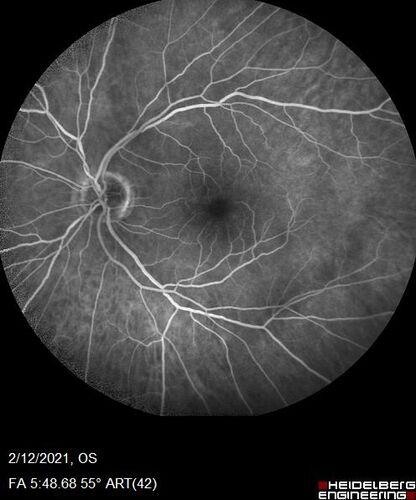

Branch Retinal Vein Occlusion with Venous Macroaneurysm (collateral)

66 year old female Did not notice vision loss in the right eye.  The right eye has been a little worse than the left but now is much worse.  Picked up during annual eye examination.  VA had been 20/20 in 5 years ago.

History of brain and spinal cord radiation 1986 for T-cell lymphoma.  Now with breast cancer, ablation for tachycardia, HTN

VA OD 6/200, OS 20/32